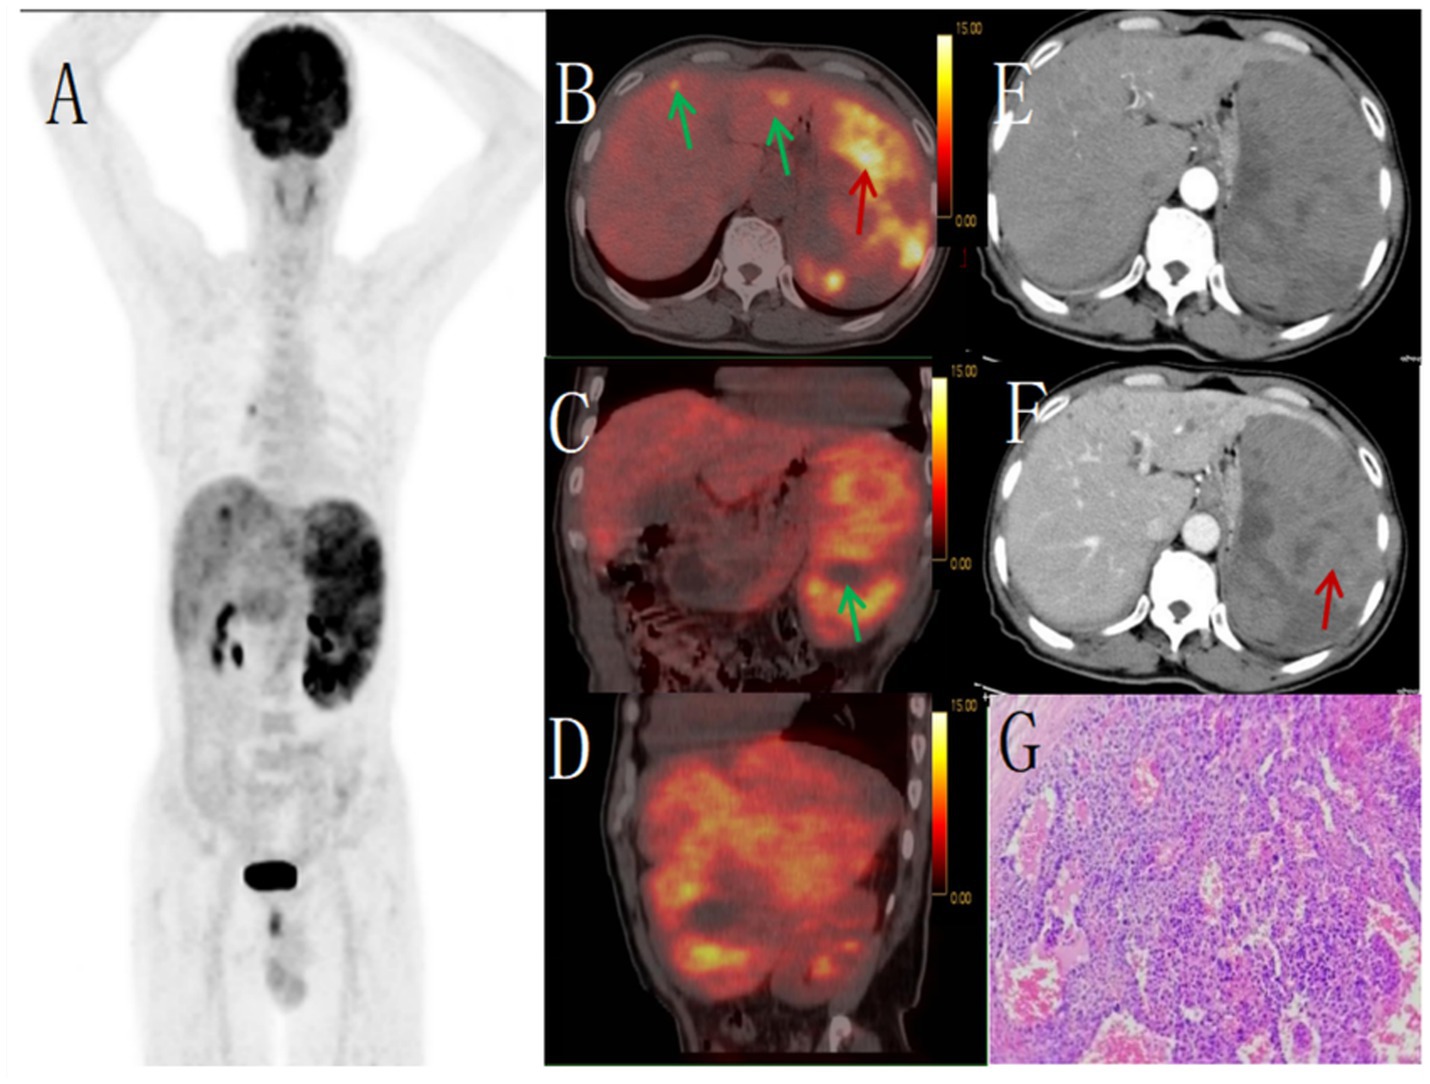

Figure 2

Male, 67 years old, primary splenic angiosarcoma. (A) whole body MIP, (B) axial fusion, (C) coronal fusion, (D) sagittal fusion, (E) enhanced CT-arterial phase, (F) enhanced CT-venous phase, (G) (H-E × 400). 18F-FDGPET/CT showed multiple nodular and massive lesions in the spleen with multiple necrotic areas, PET/CT images showed an abnormal increase in diffuse and uneven uptake of 18F-FDG in the spleen, with a SUVmax of 9.0 (red arrow, B) and no FDG uptake in some necrotic areas (green arrow, C). There were multiple nodular lesions in the liver, the level of FDG metabolism increased, the SUVmax was 5.6 (green arrow, B). Enhanced CT showed diffuse uneven mild enhancement of spleen, and the degree of enhancement increased with time (red arrow, F). Multiple nodular low-density shadows were seen in the liver, which were slightly enhanced by enhanced scan. PET/CT-guided splenic biopsy confirmed the diagnosis of primary splenic angiosarcoma (G).